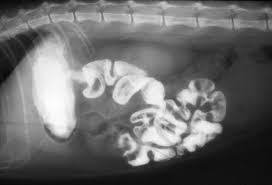

images

2枚目のレントゲン写真は、皆さんも健康診断で一度はされたことがあるかと思いますが、バリウム検査ですね。バリウム剤を飲ませて何分後から何回に分けてレントゲン撮影をします。胃腸の動きに問題がなければ、最後まで流れますが(結腸や直腸といわれる大腸まで)、途中でバリウムが一切流れなくなったり、写真でも写っているように腸自体の動きが異常をきたしていると(写真ではぐにゃぐにゃ)、腸閉塞などを疑って診断していきます。